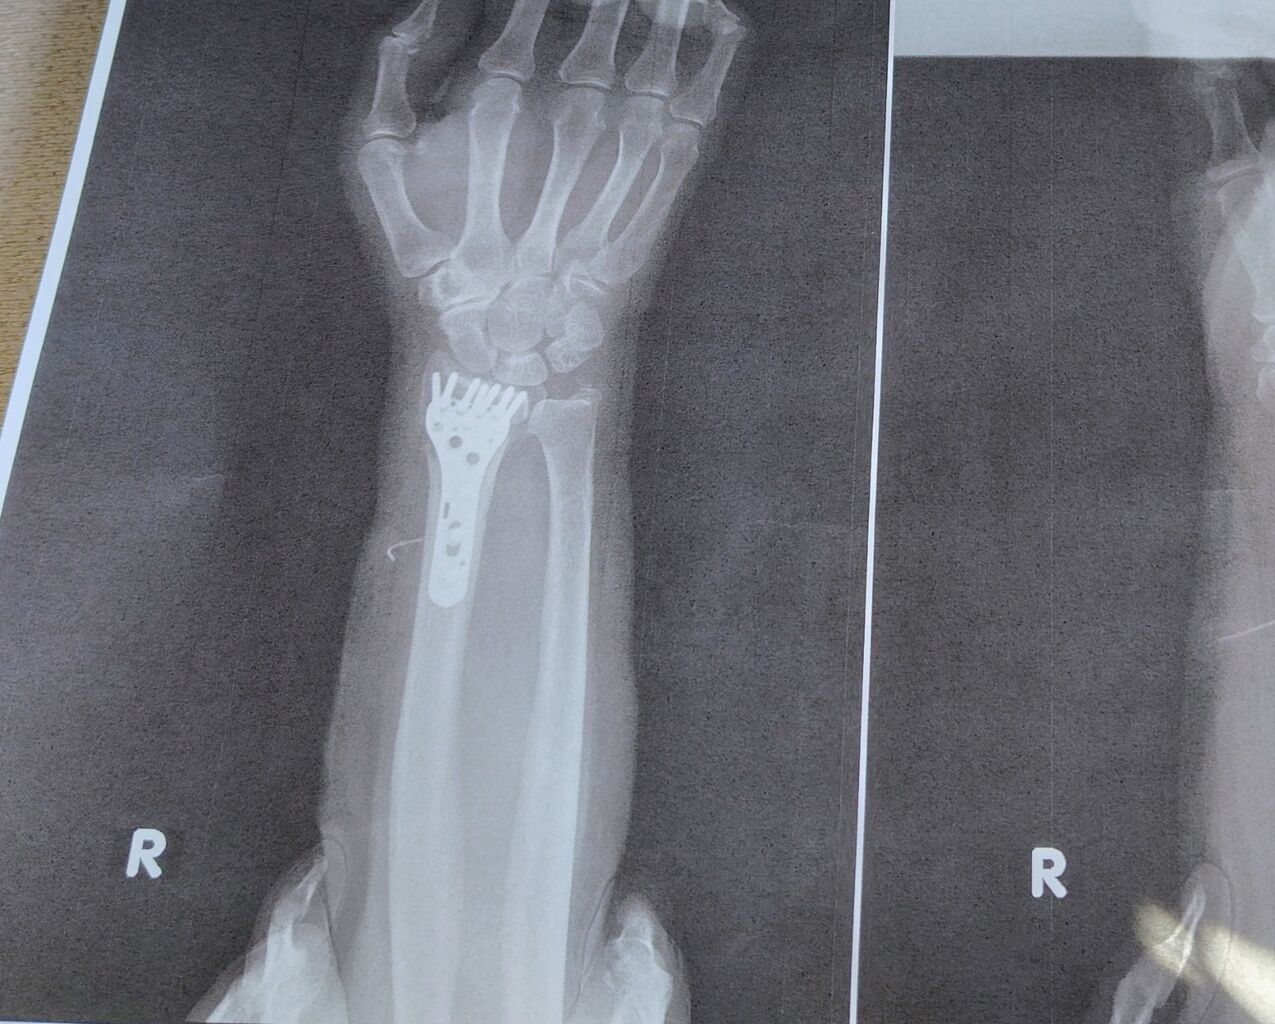

金属のプレートとネジがしっかり写っています。

痛そうだけど、無事終わってホッとしました。